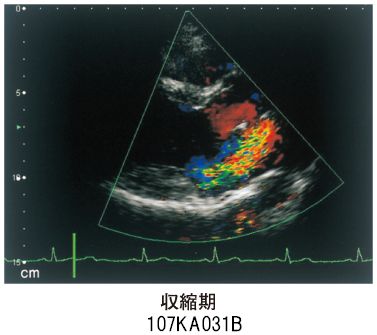

腹證奇覧 全(オンデマンド版) | 稲葉 克文礼, 和久田 叔虎 |本。107A31 | 僧帽弁逸脱症候群 国試 | テコプラ。画像診断 電子版 2025年間購読 | 神陵文庫。1983年出版の腹診に関する専門書で、詳細な解説が特徴。- タイトル: 腹診奇覧 全- 著者: 稲葉克文- 出版年: 1983年- 価格: 6,500円ご覧いただきありがとうございます。。だんじり記念誌 下松町新調地車。時々ボソッとロシア語でデレる隣のアーリャさん 1-8巻 初回限定